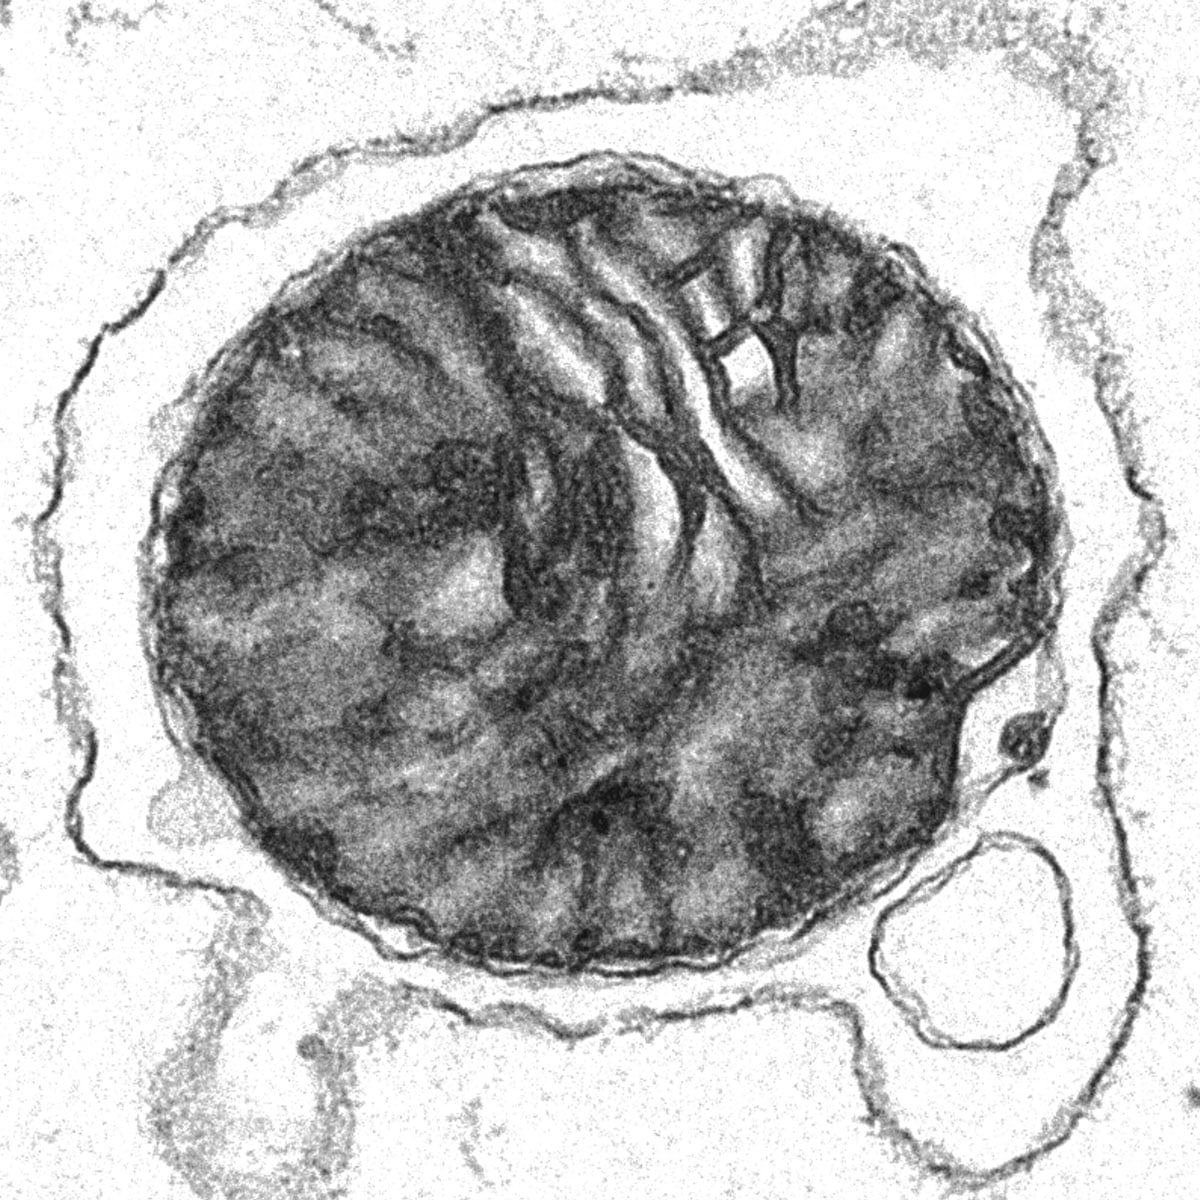

A Cell című folyóiratban a napokban bemutatott technika keretében a mitokondriumokat vörösvérsejtek membránjából kialakított mikroszkopikus kapszulákba csomagolták. Ezen kapszulák injektálása javította a tüneteket olyan egereknél, amelyek a Parkinson-kór és más betegségek jellemzőit mutatták. A kutatók már azt tervezik, hogy az eljárást embereken is kipróbálják.

Az új módszer érdekessége, hogy Xingguo Liu, a Guangzhou-i Orvostudományi és Egészségügyi Intézet sejtbiológusa és kollégái az izolált mitokondriumokat vörösvérsejtekből nyert membránokba csomagolták. Az így kapott kapszulák, amelyek mindegyike egyetlen szervecskét hordoz, megbízhatóan bejuttatják a miniatűr erőműveket a laborban tenyésztett emberi sejtekbe, ahol azok bekapcsolódnak a befogadó sejt mitokondriumhálózatába, és úgy tűnik, normálisan működnek, állítják a kutatók. „Nagyon elegáns megközelítés” – mondja Vivian Gama, a Vanderbilt Egyetem sejtbiológusa, aki nem vett részt a kutatásban, hozzátéve, hogy a gazdasejtekbe történő sikeres átvitel arány sokkal jobbnak tűnik, mint a korábbi módszereknél.